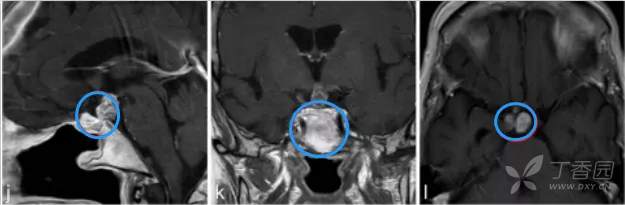

j、k、l图显示,肿瘤得到全切,术后2年无复发,目前孩子在接受激素替代疗法